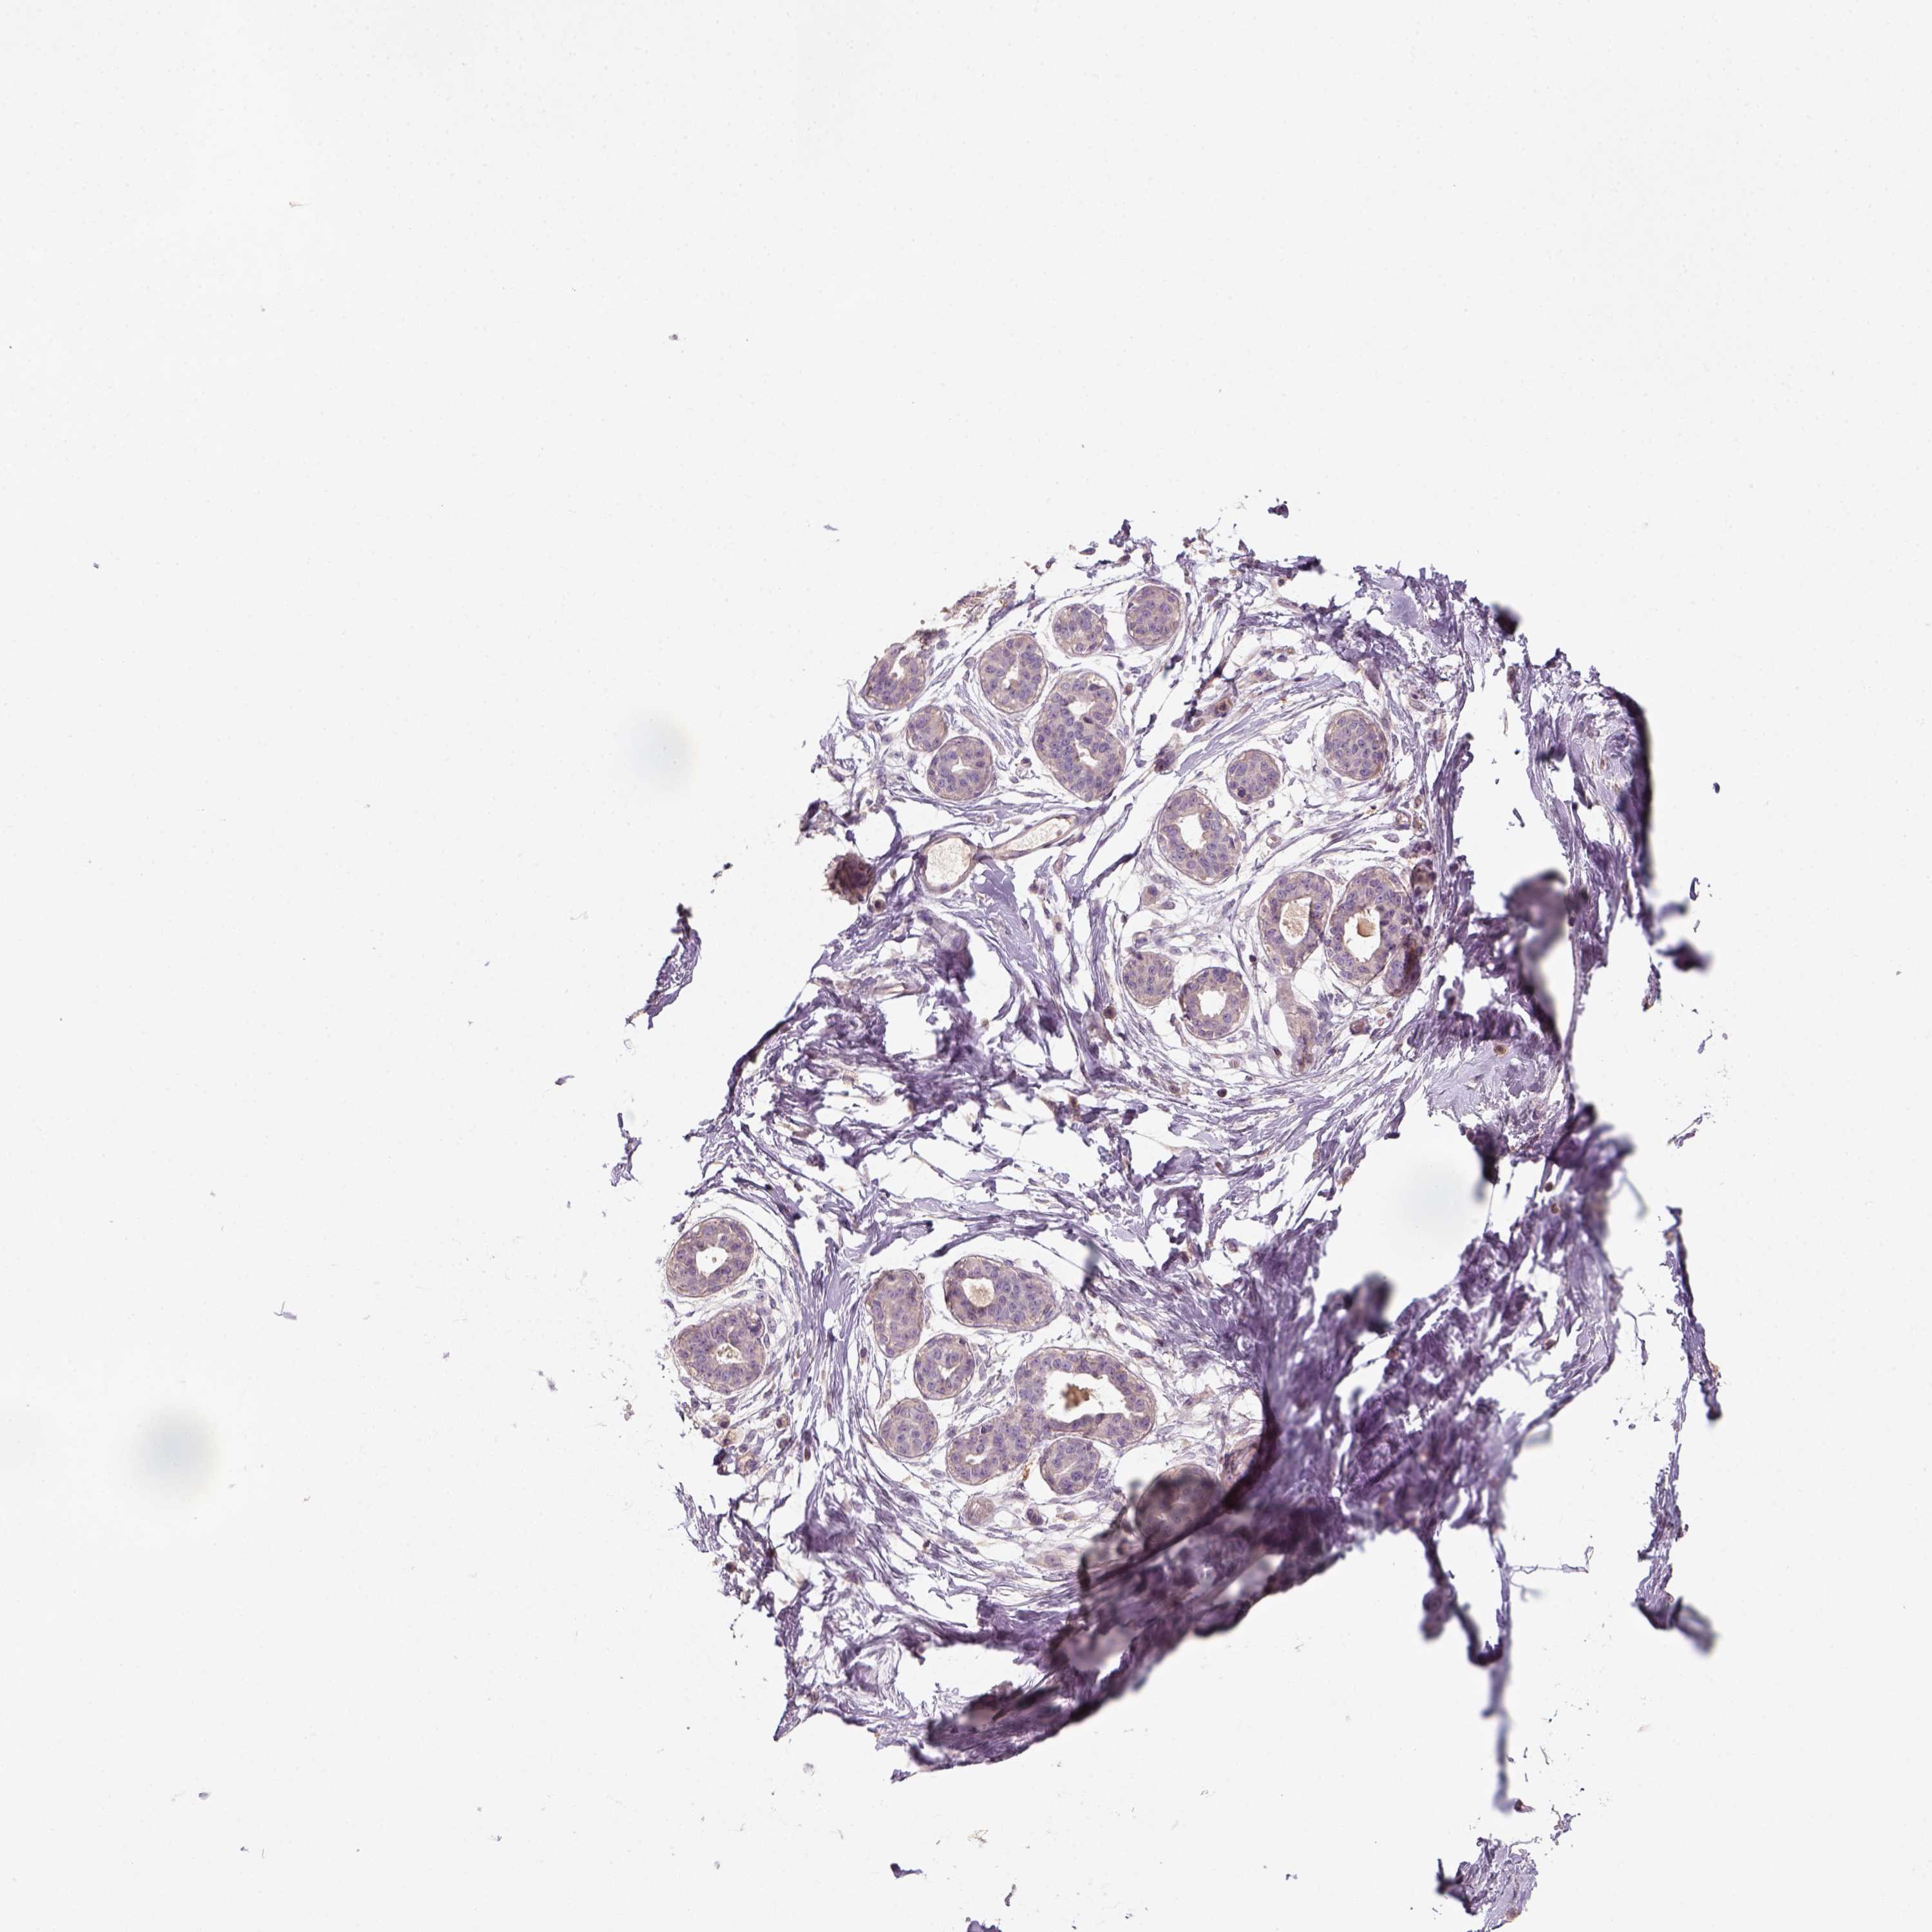

TISSUE PRIMARY DATA BREAST Show tissue menu

Breast

BREAST - Antibody stainingi

Antibody staining in the annotated cell types in the current human tissue is reported as not detected, low, medium, or high, based on conventional immunohistochemistry profiling in selected tissues. This score is based on the combination of the staining intensity and fraction of stained cells.

Each image is clickable and will lead to virtual microscopy that enables deeper exploration of all samples and also displays staining intensity scores, fraction scores and subcellular localization as well as patient and tissue information for each sample.

Antibody HPA074762Antibody CAB075684

Adipocytes Not detectedNot detected

Glandular cells Not detectedNot detected

Myoepithelial cells Not detectedNot detected